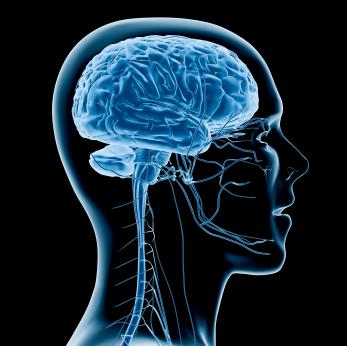

About half of patients report neurological symptoms, including headaches, confusion and delirium.

A new study offers the first clear evidence that in some people, the coronavirus invades brain cells, hijacking them to make copies of itself, according to an article in The Independent newspaper.

The virus also seems to suck up all of the oxygen nearby, starving neighbouring cells to death.

The study was posted online on Wednesday and has not yet been vetted by experts for publication. But, according to the article, several researchers said it was careful and elegant, showing in multiple ways that the virus can infect brain cells.

Scientists have had to rely on brain imaging and patient symptoms to infer effects on the brain, but “we hadn’t really seen much evidence that the virus can infect the brain, even though we knew it was a potential possibility,” said Dr Michael Zandi, consultant neurologist at the National Hospital for Neurology and Neurosurgery in Britain. “This data just provides a little bit more evidence that it certainly can.”